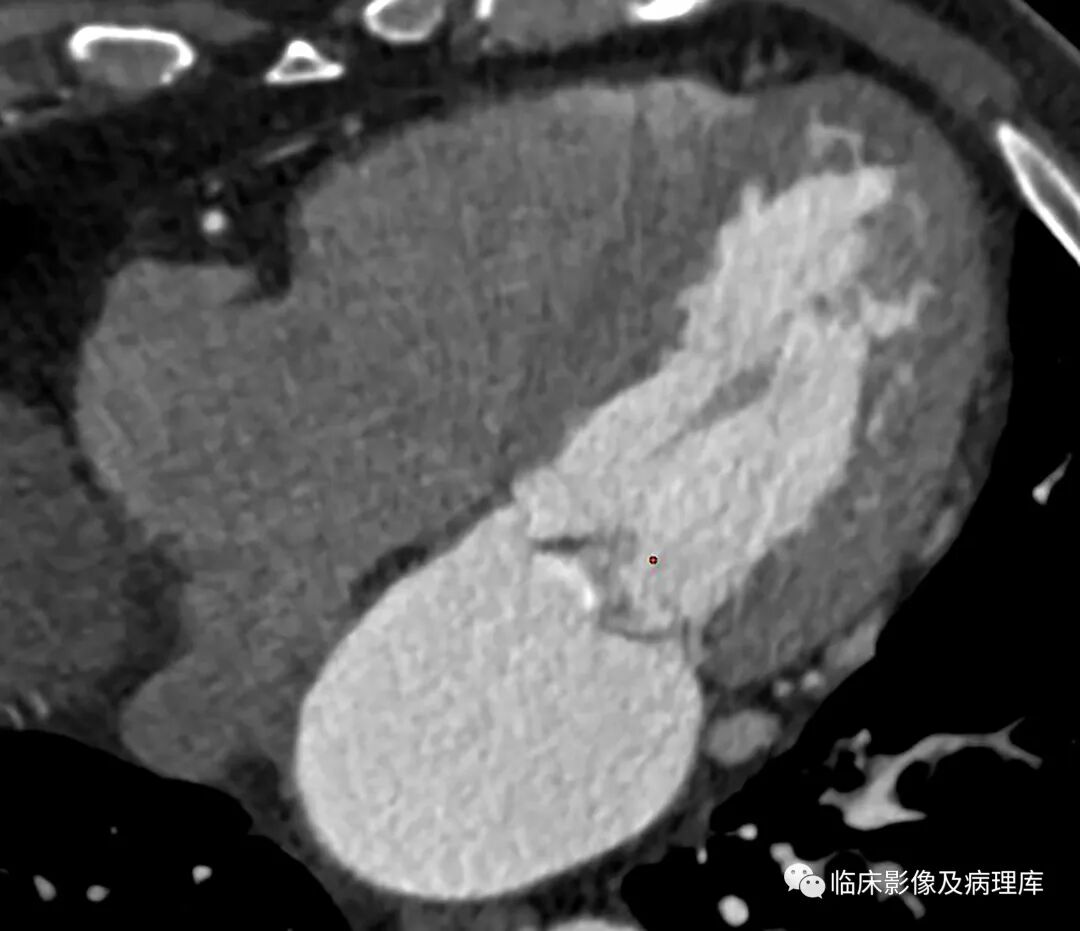

二尖瓣脱垂CT表现

上图分别为轴位及心室长轴位,显示收缩期二尖瓣后叶突向左心房内